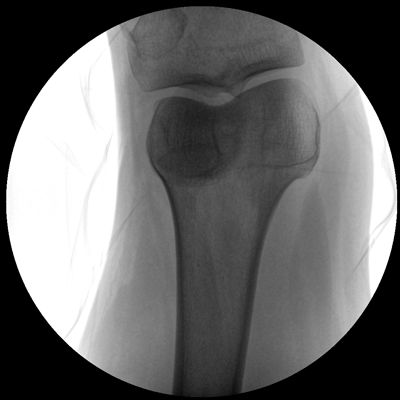

小巧輕便 超凡靈動(dòng) PLX C1116

●全數(shù)字化百萬(wàn)像素影像系統(tǒng),圖像清晰